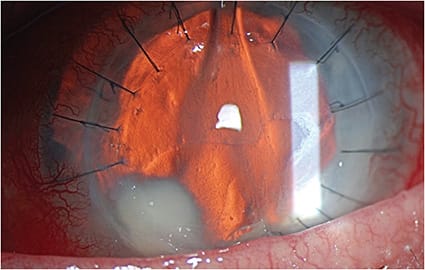

• Microsporidia keratitis. Microsporidia are intracellular protozoa that can infect the cornea. It can affect the stroma in immunocompetent eyes and appear more superficially in immunosuppressed patients. Microsporidia appear as smoldering, diffuse, multifocal stromal lesions, with lid edema and a congested conjunctiva1 (Figure 1). Patients report recurrent redness, pain, photophobia, watering, and reduced vision. This can be mistaken for HSV keratitis.

• Fungal keratitis. These atypical corneal infections are often indolent in nature. They can have less inflammation with less edema and injection initially versus all other forms of keratitis. Fungal keratitis may present clinically with an infiltrate without an epithelial defect for some patients. Red flags for this atypical form of keratitis are the presence of an infiltrate that has irregular feathery edges, an endothelial plaque, or the presence of a satellite lesion. Candida, as an example, often presents as a superficial, white-raised lesion (Figure 2). Hyphae indicate filamentous fungi, like Aspergillus or Fusarium (Figure 3).